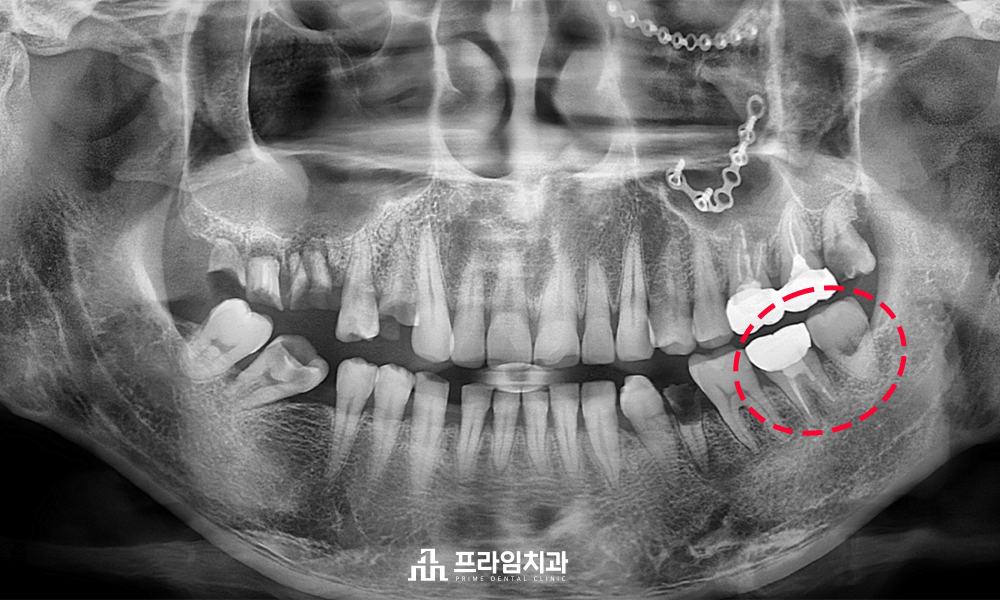

환자분께서는 타 치과에서

너무 많은 개수의 치아 발치를

권유받으셨다고 하셨는데요.

전반적으로 치료할 치아가 많다 보니,

치료를 진행할 때에 하나의 치아라도

발치를 덜 하고 살려 쓸 수 있는 치아는 살려서

쓰시기를 희망하신다며 내원해 주셨습니다.

뿌리만 남아있거나, 충치가 심한 치아는

불가피하게 발치 후 임플란트가 필요하였지만

왼쪽 아래 어금니 부위의 경우에는 다행히

사랑니가 문제없이 건강하게 존재하고 있었으므로

예후가 좋지 않은 어금니를 발치한 후

사랑니를 그 자리에 이식하는

치아이식술을 진행해 보기로 결정하였습니다.